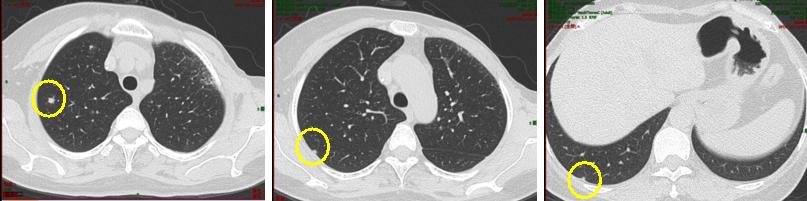

2020.5.11复查PET-CT:双肺及胸膜下多发结节,部分代谢稍高,考虑多为转移性病变;胸骨骨质代谢轻度增高(图1-1)。全身骨ECT:胸骨下段骨质代谢异常活跃,与前次比较变化不明显。

图1-1